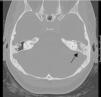

Malacoplaquia con afectación de oído medio

Malakoplakia of the middle ear